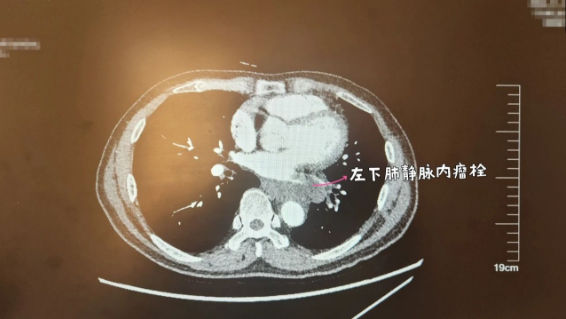

“从心包入手,先找到下肺静脉……”简单的交流后,团队迅速捋清思路。团队判断,老康的肿瘤是从左肺下叶生长出来的,而切除左肺下叶需要临时阻断与之相连的下肺动脉、下叶气管和下肺静脉,偏偏肿瘤紧紧地包绕着老康的下肺静脉。“能不能把肿瘤‘连根拔掉’,关键就在下肺静脉。”陈雯辉说。

进展顺利,手术团队顺利地打开心包,阻断老康的下肺动脉和下叶气管,此时,这台手术最关键的下肺静脉完全暴露在视野中。更大的难题接踵而来:肿瘤占据了胸腔大部分空间,医生们能使用的空间十分狭小,在这种条件下解剖下肺静脉,必然会牵拉心脏,这样就可能导致患者心律失常甚至心跳骤停。同时,老康的左肺下叶静脉中,还有一个危险的瘤栓,一旦手术中突然脱落,同样也会危及老康的生命。